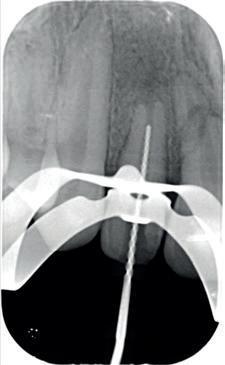

10-11. Vier weken na het trauma is de TTS verwijderd en de endodontische behandeling aan element 11 voltooid. Vanwege de brede apicale diameter is er afgesloten met MTA).

12. Röntgenbeeld 3 maanden na het trauma. Met dank aan Tristan Staas.